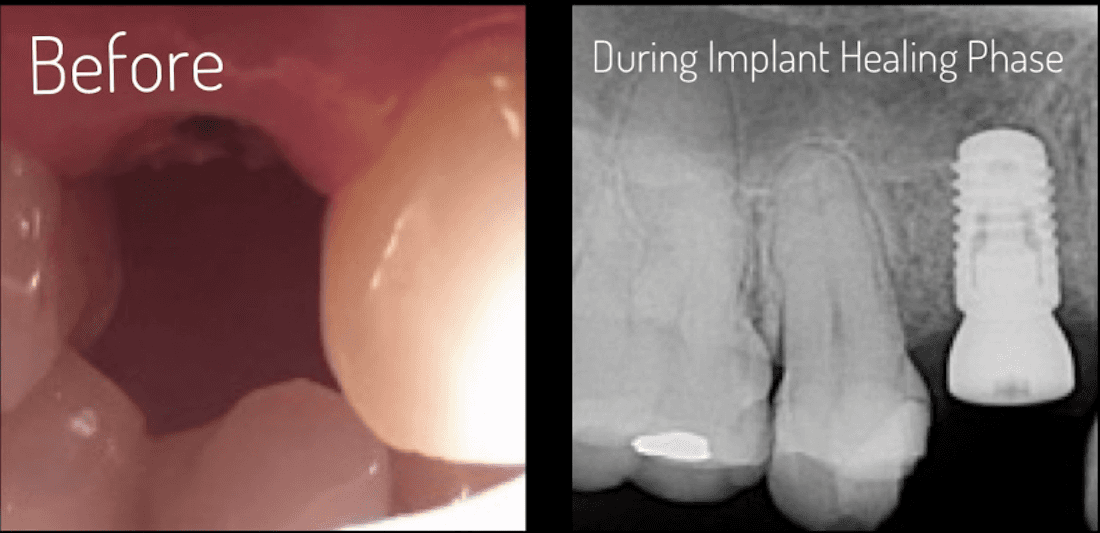

Experience the transformative power of dental implants at its finest. Our precision placement and advanced techniques ensure that each dental implant seamlessly integrates with your natural smile, providing a permanent and reliable solution for missing teeth.

Whether it's a single tooth or multiple teeth, our expertise in dental implants can restore your smile and boost your confidence, allowing you to enjoy life to the fullest.